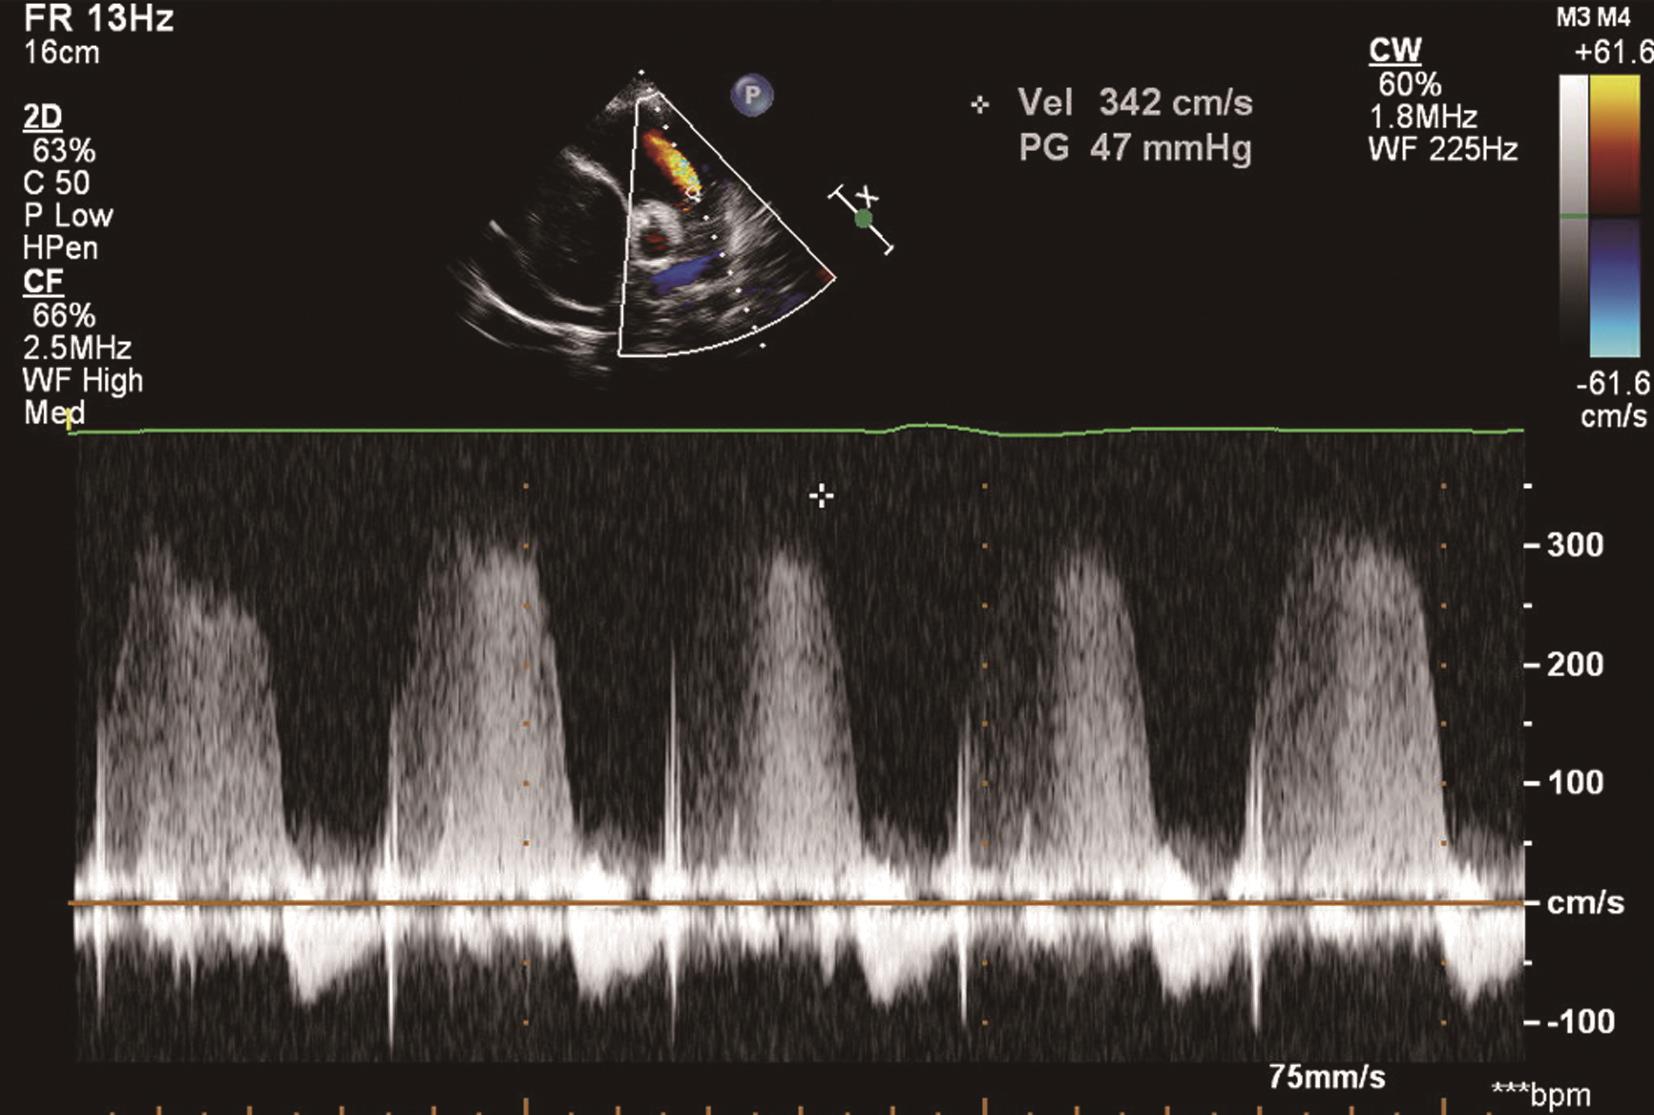

(1)心尖四腔心及大动脉短轴切面收缩期可探及花彩血流自右心室经三尖瓣反流入右心房,连续波多普勒可探及频谱呈收缩期位于基线下方的负向频谱(图6-2-2),并可测量反流的峰值流速以估测肺动脉收缩压。

图6-2-2 连续波多普勒显示三尖瓣频谱呈负向高速频谱

肺动脉收缩压(SPAP)、肺动脉平均压(PAPm)和肺动脉舒张压(PAPd)的计算公式:SPAP=4×三尖瓣反流峰值速度 2 +右心房压。

三尖瓣反流是临床最常用的筛选肺动脉高压量化指标。通常采取胸骨旁、心尖和剑突下三尖瓣标准切面,利用彩色多普勒证实三尖瓣反流的存在,再用连续多普勒测量三尖瓣反流峰值流速。为避免低估三尖瓣反流速度,应仔细调整声束方向,尽量使声束方向与取样线平行。在少数情况下,需要使用声学造影剂来获取更为清晰的三尖瓣反流频谱。在不合并肺动脉瓣狭窄及右心室流出道梗阻时,肺动脉收缩压(SPAP)等于右心室收缩压(RVSP)。可通过多普勒超声心动图测量收缩期右心室与右心房压(RAP)差来估测RVSP。按照改良柏努力公式,右心房、室压差大约等于4V max 2 ,V max 是三尖瓣最大反流速度(m/s)。RVSP=4V max 2 +RAP。RAP可通过超声心动图测量下腔静脉宽度或通过查体观察颈静脉搏动幅度来估测。成人患者下腔静脉(IVC)≤18mm,RAP=5mmHg;IVC≥18mm,吸气时 IVC塌陷≥50%,RAP=10mmHg,吸气时IVC塌陷≤50%,RAP=15mmHg。